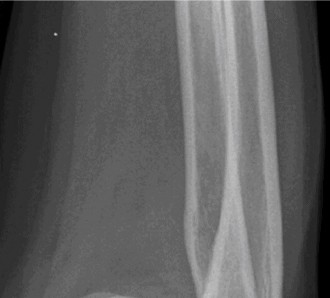

Figure 2–47 The size of the humeral head defect can be calculated by dividing the arc of impaction (x) by the total articular surface arc (y).